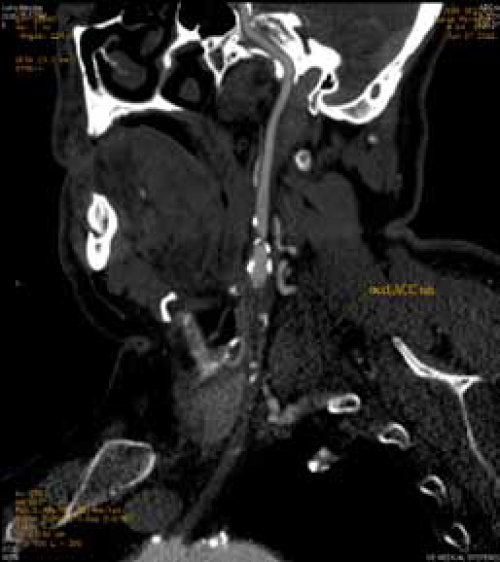

Visokostepena stenoza karotidne bifurkacije (80%) heterogenim plakom sa ulceracijom prema unutrašnjoj karotidnoj arteriji. MSCT potvrdjuje subokluziju karotidne bifurkacije i isključuje proksimalne i distalne lezije.

Krataka segmentna aterosklerotična okluzija unutrašnje karotidne arterije. Prikazuje se spoljašnja karotidna arterija sa svojim granama i plakom na orificijumu

MSCT – precizna analizua morfologije lezija supraaortalnih arterija

Skoro potpuna okluzija brahiocefaličkog trunkusa sa dugačkom totalnom trombozom zajedničke karotidne arterije levo

MSCT karotidna angiografija pruža mogućnost istovremenog sagledavanja karotidnih i drugih arterija koja koje ishranjuju mozak, ali i moždanog parenhima kao cerebralnog venskog sistema.